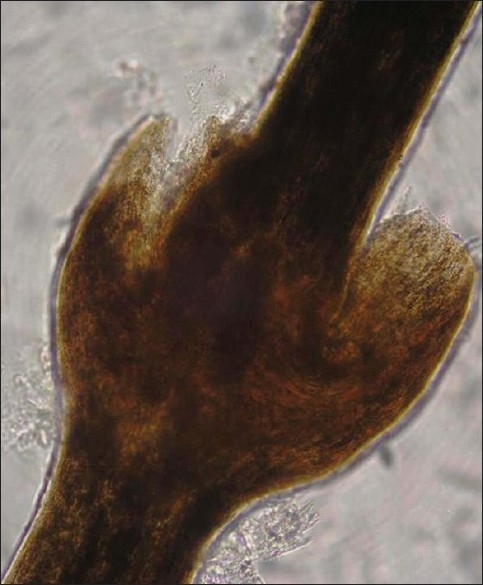

一名 24 岁的男性患者自出生以来就出现全身鳞状病变。 从小就存在皮损频繁加重和完全缓解的病史。 以复发性过敏性鼻炎为形式的特应性个人病史从孩提时代就存在。 无父母近亲史。 没有充满液体的病变史。 在一般检查中,患者适度构建和营养。 皮肤检查显示,皮损周围有多个广泛分布的环状多环状鳞状红斑,双刃鳞屑,累及躯干和四肢。 皮肤损伤在每次恶化期间不断改变其形状和大小,并且在愈合时不会留下疤痕或色素变化。 指甲有光泽。 头皮毛发稀疏、粗糙、无光泽。 黏膜等全身检查均在正常范围内。 血液检查显示血红蛋白 - 9.5 gm,白细胞计数 - 7300 个细胞/立方米,轻度嗜酸性粒细胞增多,红细胞沉降率升高 - 54 mm / h,血清 IgE 水平升高 - 11412.30 IU / ml。 头皮毛发的光学显微镜检查显示典型的毛发内陷(竹毛),毛干的远端部分内陷到近端部分。 背部病变的活组织检查与线状鱼鳞病的临床诊断一致。

图4:头皮毛发的光镜检查显示典型的内陷性毛发脱落(竹节状毛发)